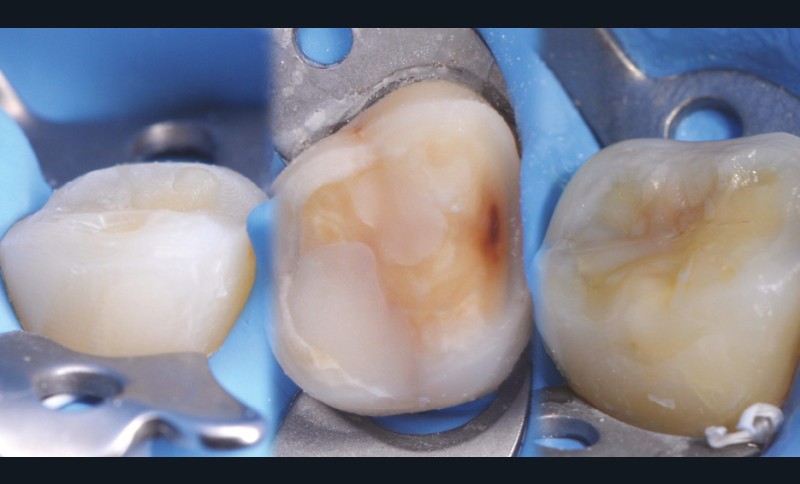

Les overlays (céramique et composite) sont devenus en quelques années un véritable référentiel en termes de restaurations partielles postérieures. Ils sont même les successeurs contemporains de la couronne périphérique dans bon nombre de situations, que ce soit sur dent pulpée présentant un délabrement coronaire important ou sur dent dépulpée pour laquelle le recours au recouvrement de la totalité de la face occlusale est souvent jugé plus indiqué (fig. 1 à 4).

à ces restaurations correspond aujourd’hui toute une série de nouveaux design postérieurs permettant une ultra-préservation tissulaire et pouvant s’inscrire, en fonction des situations cliniques, dans l’émail (situation idéale), dans la dentine, dans le composite de base intermédiaire, ou un « mix » de ces différents supports (fig. 10 à 13).

Les épaisseurs de préparation varient donc selon la nature du support. De 0,6 à 1 mm d’épaisseur sur l’émail jusqu’à 1,5 mm sur la dentine ou le composite afin d’être en adéquation avec les modules d’élasticité des matériaux de restauration utilisés (céramique ou composite).